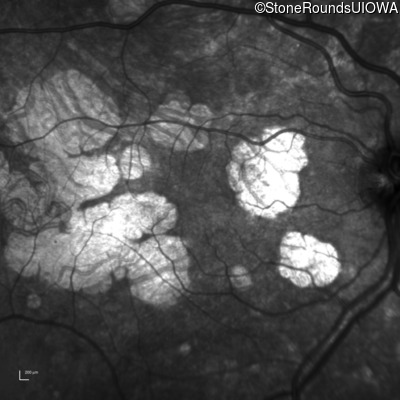

Infrared Fundus Photograph - Right - 20/20

Exemplar